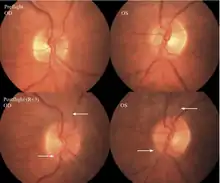

The first U.S. case of visual changes observed on orbit was reported by a long-duration astronaut that noticed a marked decrease in near-visual acuity throughout his mission on board the ISS, but at no time reported headaches, transient visual obscurations, pulsatile tinnitus or diplopia (double vision). His postflight fundus examination (Figure 1) revealed choroidal folds below the optic disc and a single cotton-wool spot in the inferior arcade of the right eye. The acquired choroidal folds gradually improved, but were still present 3 year postflight. The left eye examination was normal. There was no documented evidence of optic-disc edema in either eye. Brain MRI, lumbar puncture, and OCT were not performed preflight or postflight on this astronaut.[5]

The sixth case of visual changes of an ISS astronaut was reported after return to Earth from a 6-month mission. When he noticed that his far vision was clearer through his reading glasses. A fundus examination performed 3 weeks postflight documented a grade 1 nasal optic-disc edema in the right eye only. There was no evidence of disc edema in the left eye or choroidal folds in either eye (Figure 13). MRI of the brain and eyes days postflight revealed bilateral flattening of the posterior globe, right greater than left, and a mildly distended right optic nerve sheath. There was also evidence of optic-disc edema in the right eye. A fundus examination postflight revealed a "new onset" cotton-wool spot in the left eye. This was not observed in the fundus photographs taken 3 weeks postflight.[5]

The seventh case of visual changes associated with spaceflight is significant in that it was eventually treated postflight. Approximately 2 months into the ISS mission, the astronaut reported a progressive decrease in his near and far acuity in both eyes. The ISS cabin pressure, CO2 and O2 levels were reported to be within normal operating limits and the astronaut was not exposed to any toxic substances. He never experienced losses in subjective best-corrected acuity, color vision or stereopsis. A fundus examination revealed a grade 1 bilateral optic-disc edema and choroidal folds (Figure 15).[5]